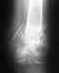

травма случилась 19 августа 1995 года был двухлодыжечный перелом правой голени поставили смешанную контрактура г-ст2 степени

синтез лодыжек проволокой и спицами по Абдрахманову.Трансарктическая фиксация г-ст спицами. ДО 2007 года я ходила с этими конструкциями, 2007 году меня прооперировали убрали спицы но улучшений не стала нога совсем не сгибается сильно отекает, наступать на правую ногу невозможно. Прошлом году на швах открылся свищ, делала снимок поставили деагнос остемелит кости. Большая просьба помогите, как мне быть. Хотелось к вам попасть на консультацию.

C остеомиелитом лучше обратиться в гнойное отделение - в Екатеринбурге это в 23 ГБ (жители города) и госпиталь ветеранов войн (жители области). Скорее всего, надо замкнуть сустав, попутно сделав обработку гнойного очага.